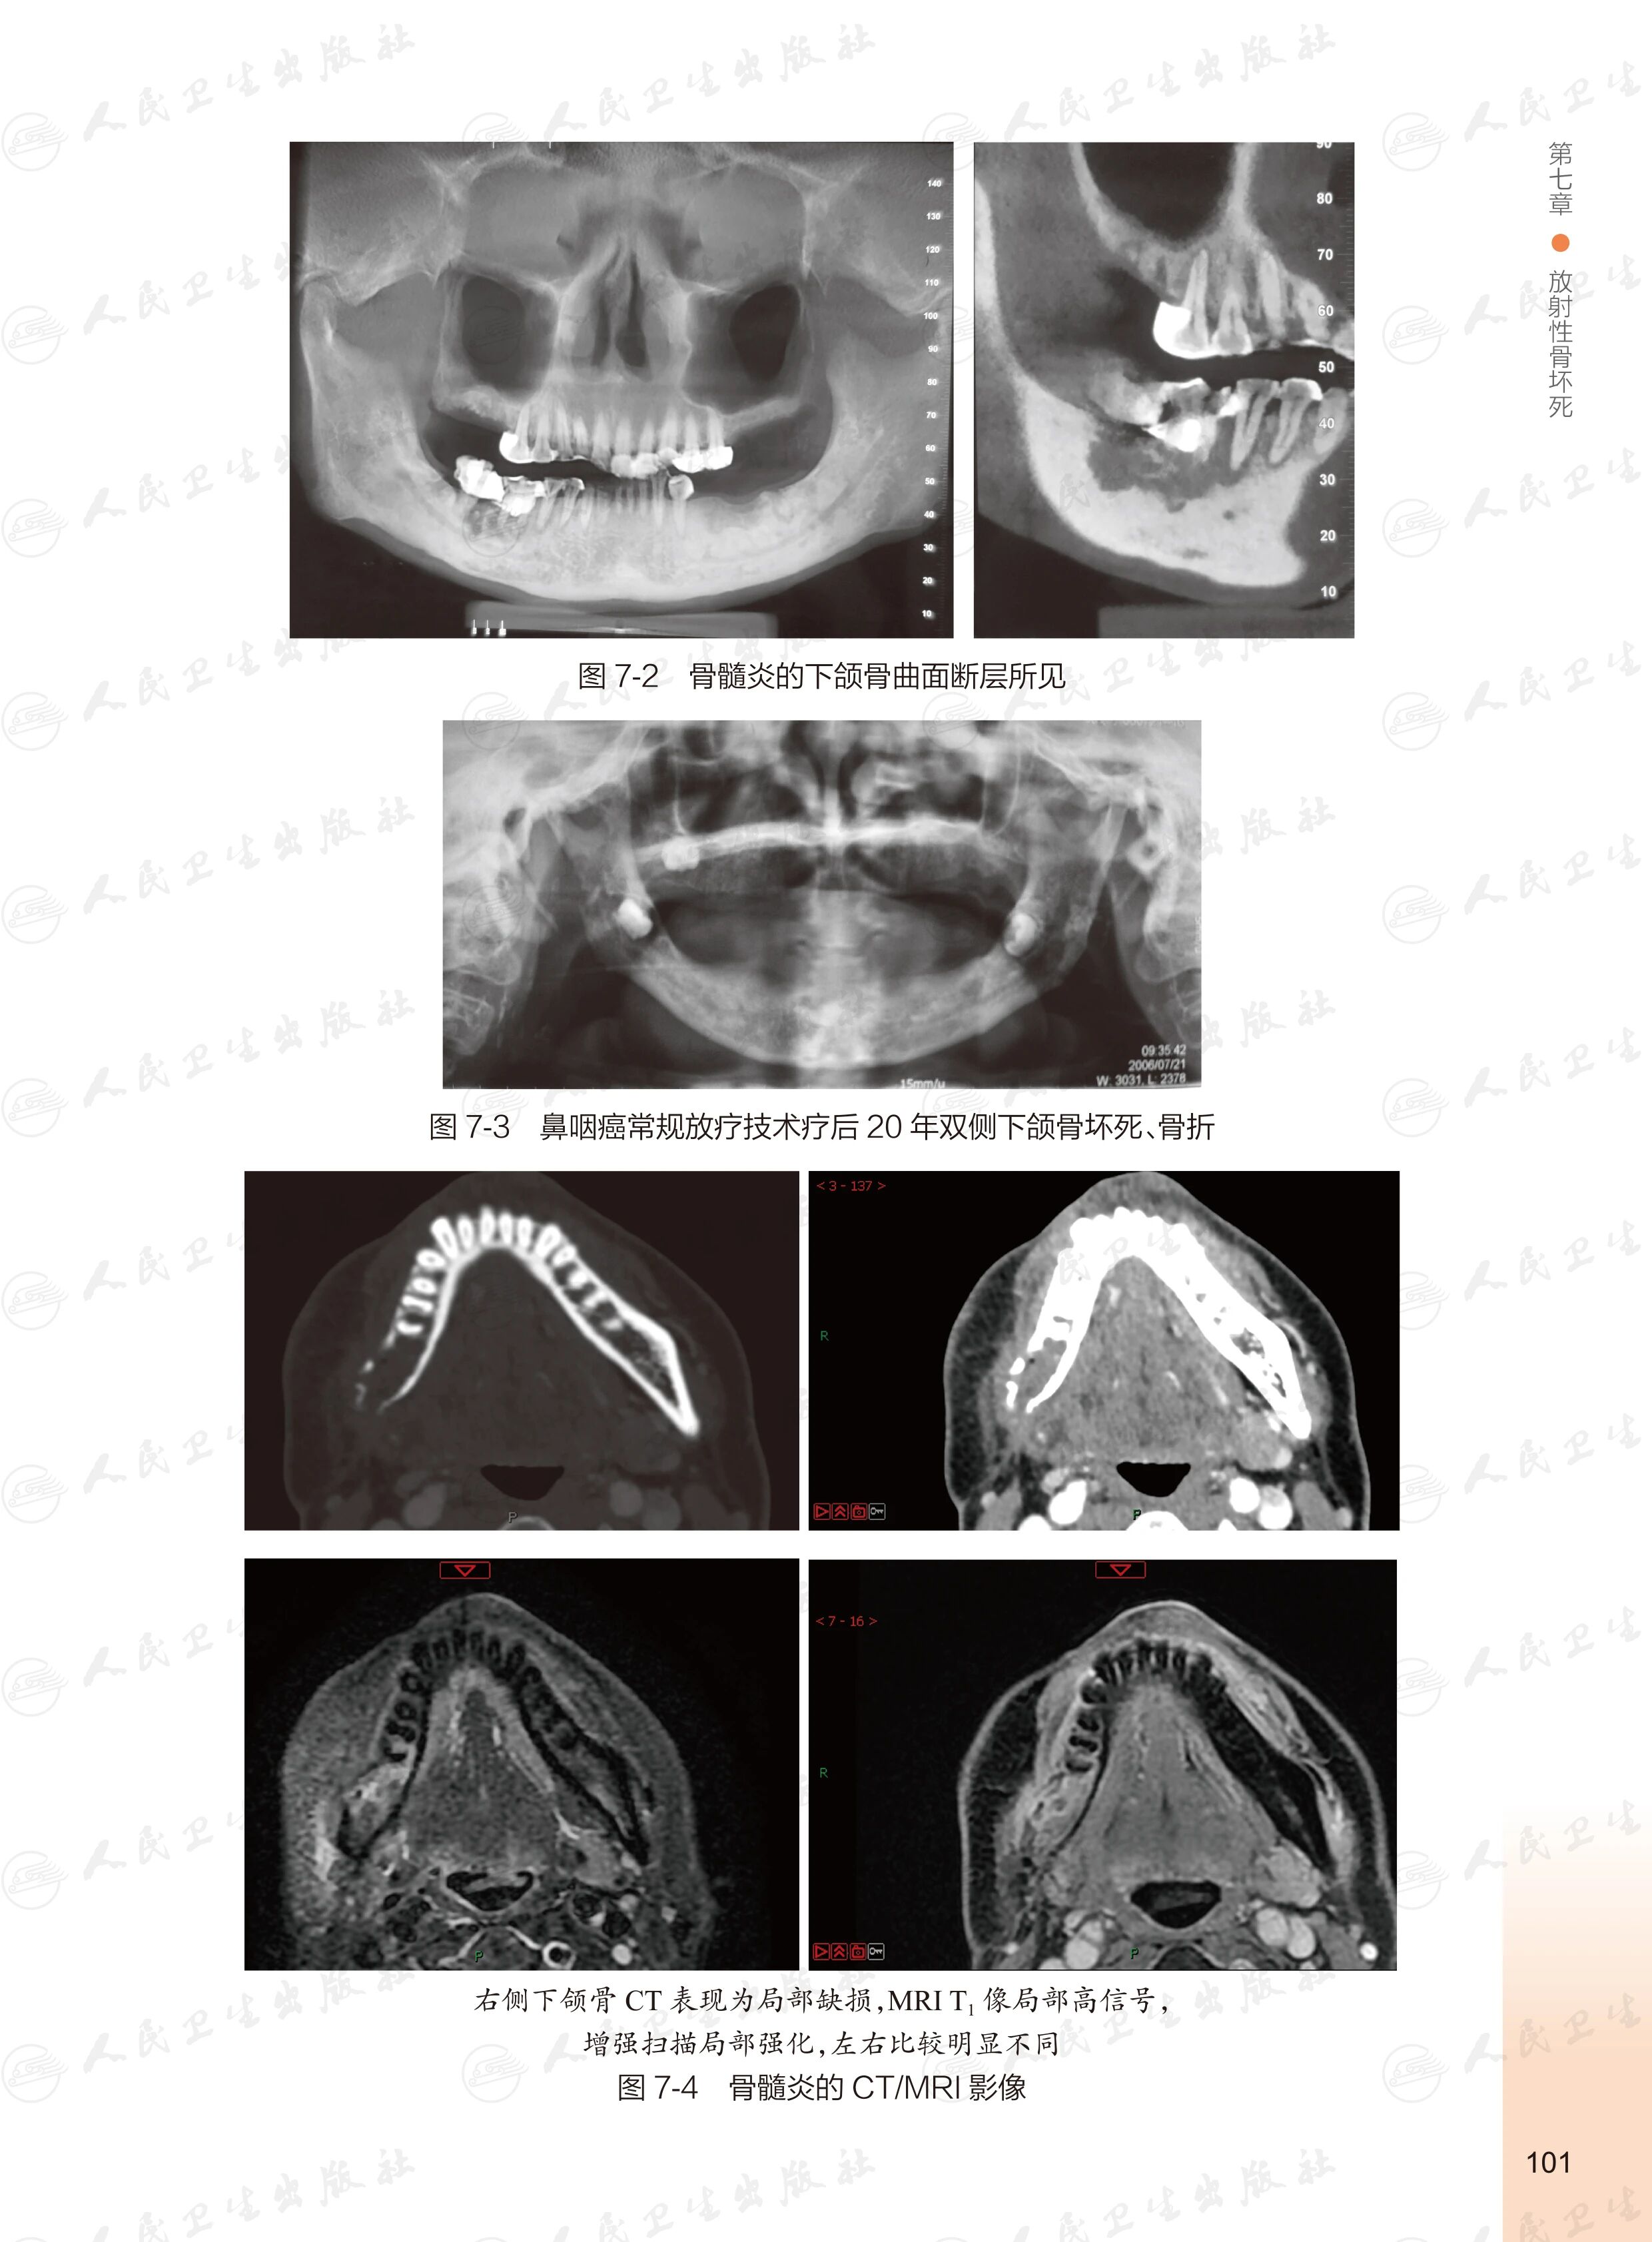

《头颈部肿瘤放射治疗并发症图谱》

——破解放疗并发症的智慧锦囊